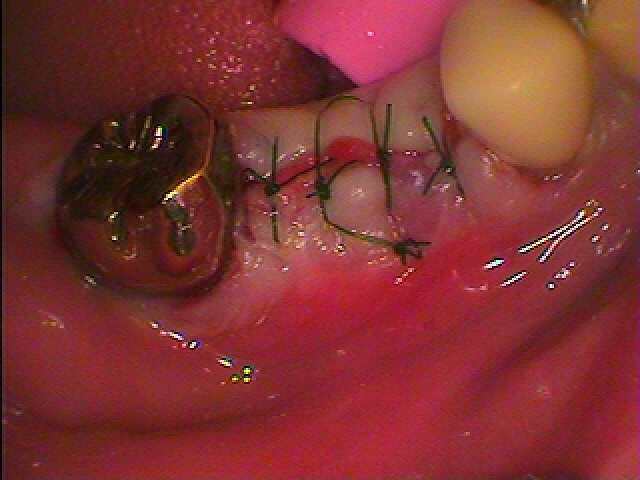

縫合して終了となります

2か月待ちましたので、抜歯して5か月後に歯茎より頭出しをしていきます